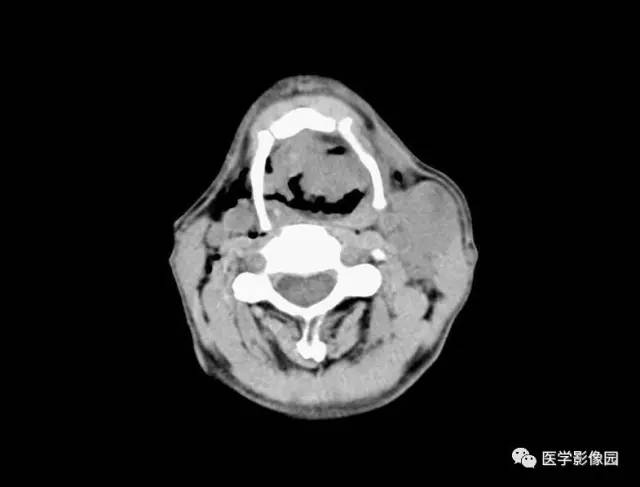

图3-5-11 声门区癌

A.CT平扫见左侧声带和前联合明显增厚,

喉腔变形,声门裂变窄(↑);

B.肿瘤向上侵犯左侧杓会厌皱襞和喉前庭